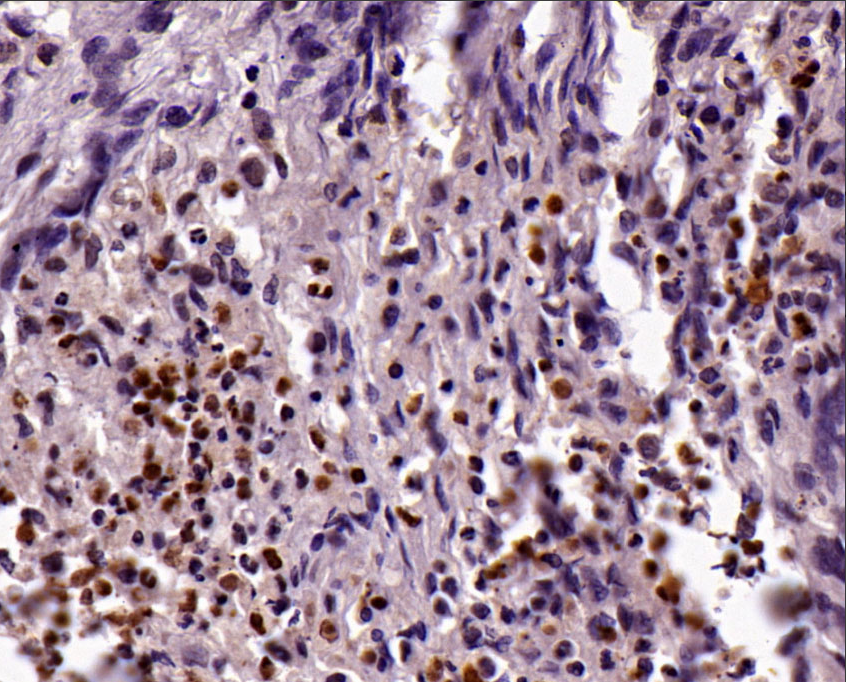

Positive controls: nerve sheath tumor, astrocytoma, brain

This antibody reacts with human GFAP and does not cross-react with other intermediate filament proteins (such as keratin, vimentin, desmin, and neurofilament). Generally, normal and tumorous astrocytes, glial cells, and ependymal cells are positive, while ganglion cells, neurons, fibroblasts, oligodendrocytes, and tumors derived from these cells are negative. GFAP is primarily used in the study of central nervous system tumors such as astrocytomas.

GFAP antibody reagents can specifically bind to GFAP molecular antigens. Immunohistochemistry kits containing GFAP antibody reagents are suitable for the classification of astrocytomas.